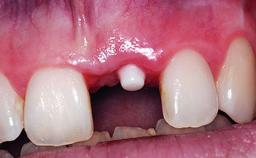

Replacement of an Upper Right Central Incisor with Root Resorption: Ridge Preservation, Delayed Placement of an NC Bone Level Roxolid Implant

A 32-year-old female Caucasian patient with a compromised maxillary right central incisor was referred to us by a general dentist. Her chief complaints were discomfort and mobility of tooth 11 with unsatisfactory esthetics due to discoloration. The patient reported a previous trauma, some years earlier, as the origin of pathology on the afflicted tooth. Anamnesis was negative for any other dental or periodontal pathology in the remaining dentition. The patient did not take any medication and reported to be a light smoker (5–10 cigs/day). She had high esthetic expectations of her treatment. The extraoral examination revealed a high smile line with full exposure of her maxillary teeth and surrounding soft tissue in the area between the second premolars.

Provisional Implant-Supported Prosthesis Prosthodontic margin > 3 mm apical to mucosal margin Prosthodontic margin > 3 mm apical to mucosal margin

Interim Prosthesis during Healing Fixed Fixed